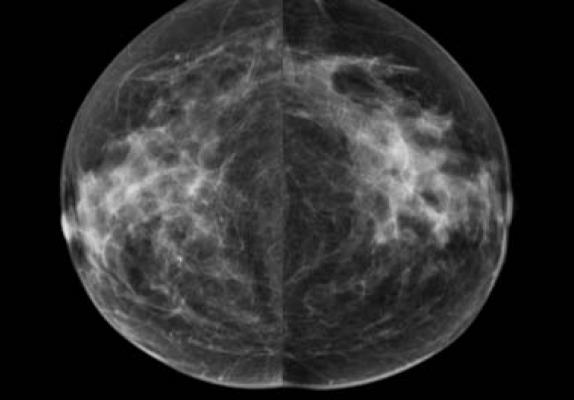

Mammography plays a critical role in the early detection of breast cancer, because it can show changes in the breast up to two years before a woman or her physician can feel them, and early detection leads to better treatment options and improved survival.